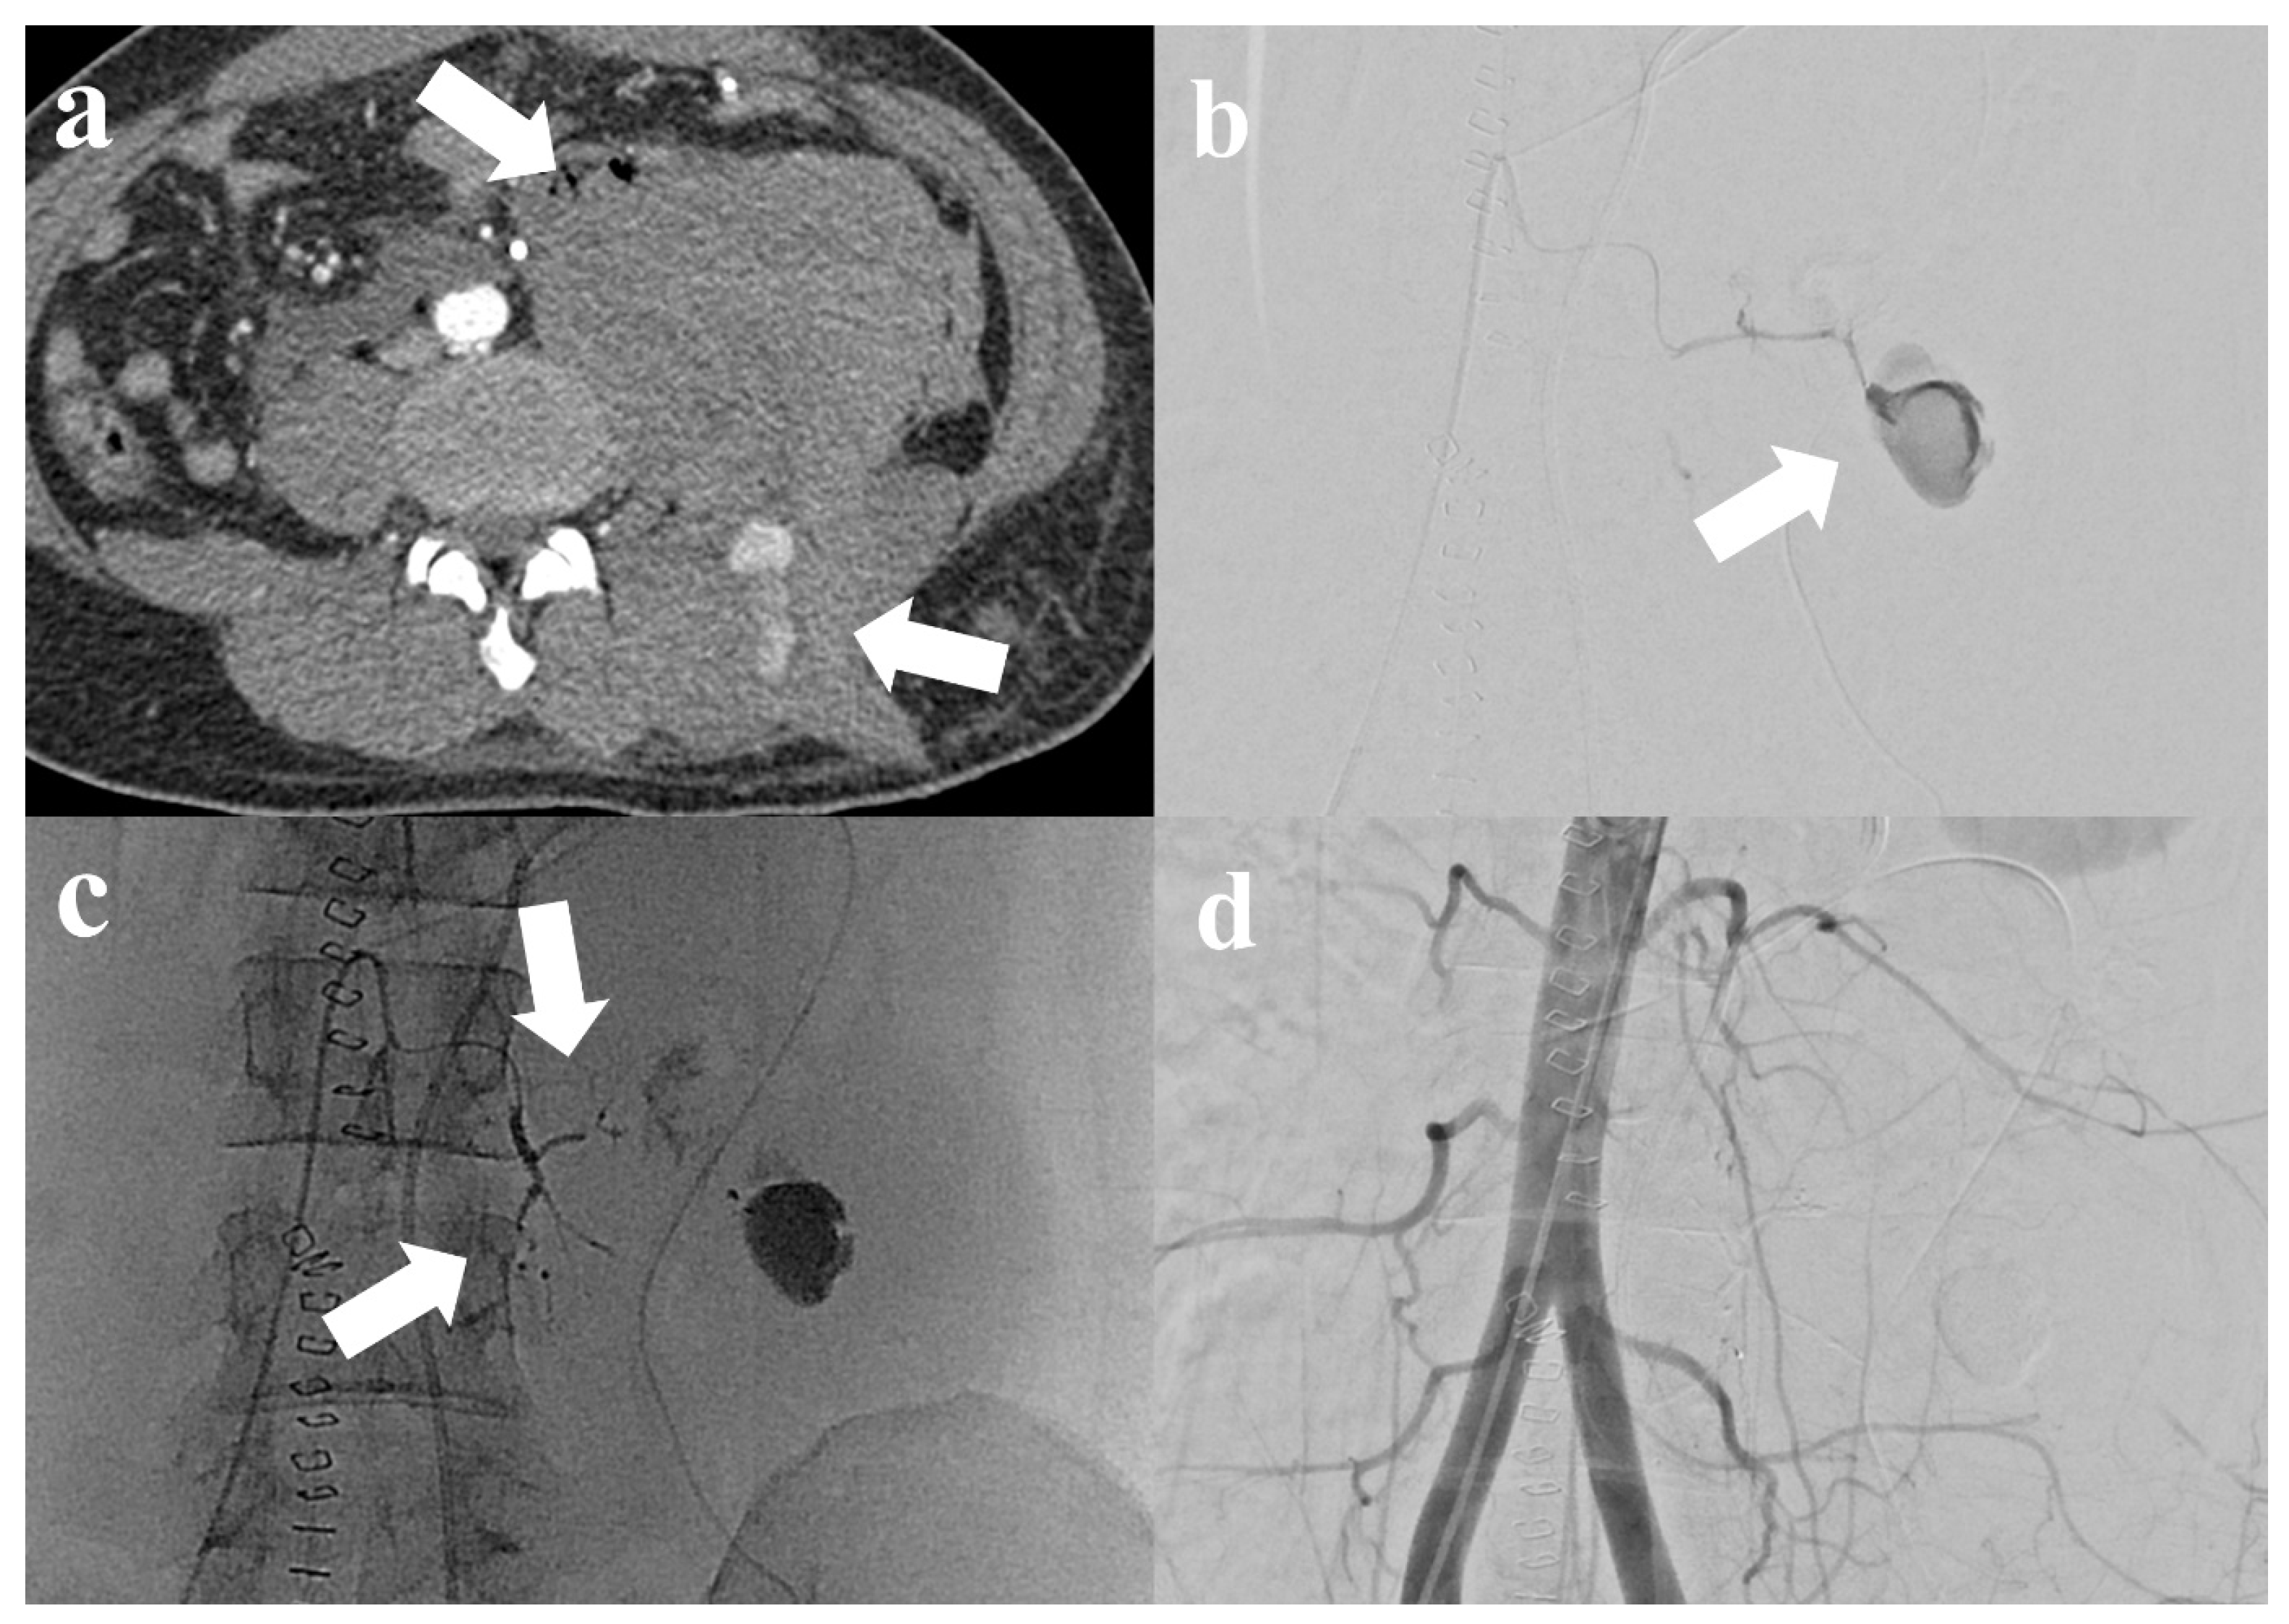

| M/29 | Neurofibromatosis | TG (Collision) | N | 103 | 1.05 | Y/Y | Left 1st, 3rd, and 4th lumbar artery (1st session) and left 2nd lumbar artery (2nd session) | 5.1 | 10 | Y → Y | 70 | Y | Clinical improvement after subsequent 2nd transarterial embolization (rebleeding from another artery and embolization was successfully performed) |